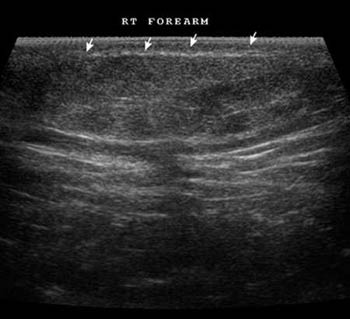

A mixed echogenic mass lesion seen in subcutaneus region, suggesting lipoma.